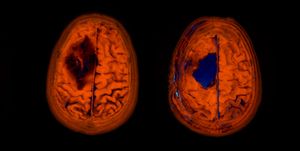

I believe there are around 4,000-5,000 images in total from 1 CT and 1 MRI scan! Thankfully there are tools that you can use to view these images. And not just view them, they allow you to navigate through all the scans. Each image is essentially a "slice" of the brain. The tools allow you to move through all 3 axis in near real time, with each of the corresponding panels changing depending on the input from the others.

In the above image you can see my MRI scan. It's essentially an orthogonal view of my head, with each of the panels represents a different axis:

- Left panel: Top of my head (Axial view)

- Top right: Front to back of my head (Coronal view)

- Bottom left: Side of my head (Sagittal view)

The solid blue line you see in the views is the current plane I have selected to see. As you move this plane, all three images change accordingly. Notice how the blue line on the axial view (left panel) matches that of the coronal view (top right) in terms of position. The resulting image in the sagittal view (bottom left) is the image that corresponds with this selection I have made.

It's so incredibly clever and absolutely fascinating (to me at least)! I spent the best part of 2-3 hours looking at my own brain scans. I wish I knew what it all meant, but I plan on quizzing the experts when I get the chance. I'd like to write a blog post all about it in the future. So, watch this space!

For those interested in doing the same the tools I used are:

Horos takes it a step further, as it allows you to view your scan in 3D, and even export an animation to show all your friends at the next soirΓ©e you attend! So yes, if you ever fancy looking at your own insides in detail, remember you can request your CT and MRI scan data!